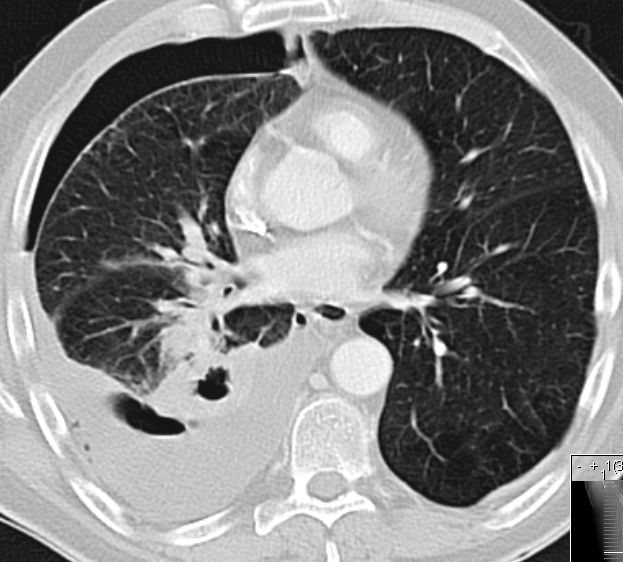

Primär zerebral metastasiertes Adenokarzinom des rechten Unterlappens. Im CT Tumor kavernenartig zerfallend. Jetzt: Sero-Pneu.

Sero-Pneu im CT